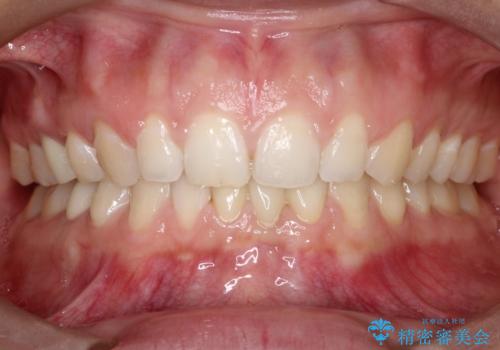

【前歯ブリッジ】下顎前歯の先天性欠如の補綴治療

後続永久歯は先天性欠如しており、下顎前歯のブリッジにて補綴治療を行なっております。

色調も周りの歯に合わせることができ、患者さんには満足していただきました。